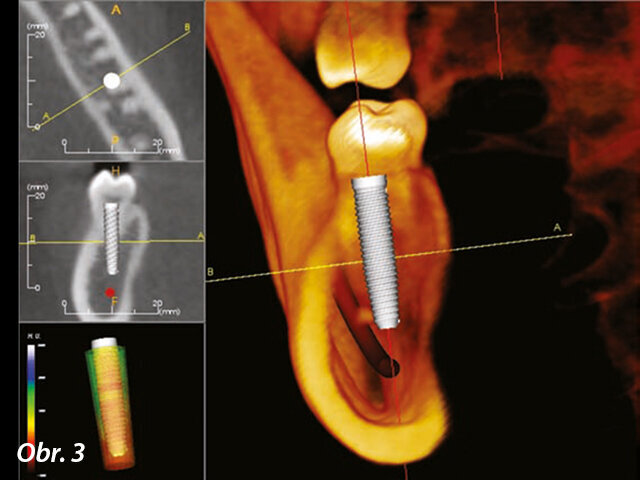

Data zachycená během skenování se ukládají ve formátu DICOM (Digital Imaging and Communications in Medicine), což je standard pro zpracování, ukládání, tisk a přenos informací v lékařských zobrazovacích metodách (Howerton et al., 2008). Přenositelnost těchto údajů umožňuje lékařům používat různé 3D plánovací programy (obr. 3). Ne všechna skenovaná data jsou vytvořena stejně: zachycená data mohou mít „digitální šum“ vlastní digitální informace. To může způsobit rozmazání 3D obrazů v nativních a nekompatibilních softwarových programech. Předtím, než investujete do určité technologie, zjistěte si, jak se data každého stroje objevují v softwaru třetích stran, nebo se zeptejte v laboratoři, která pracuje s mnoha datovými soubory, které z přístrojů mají nejmenší šum.